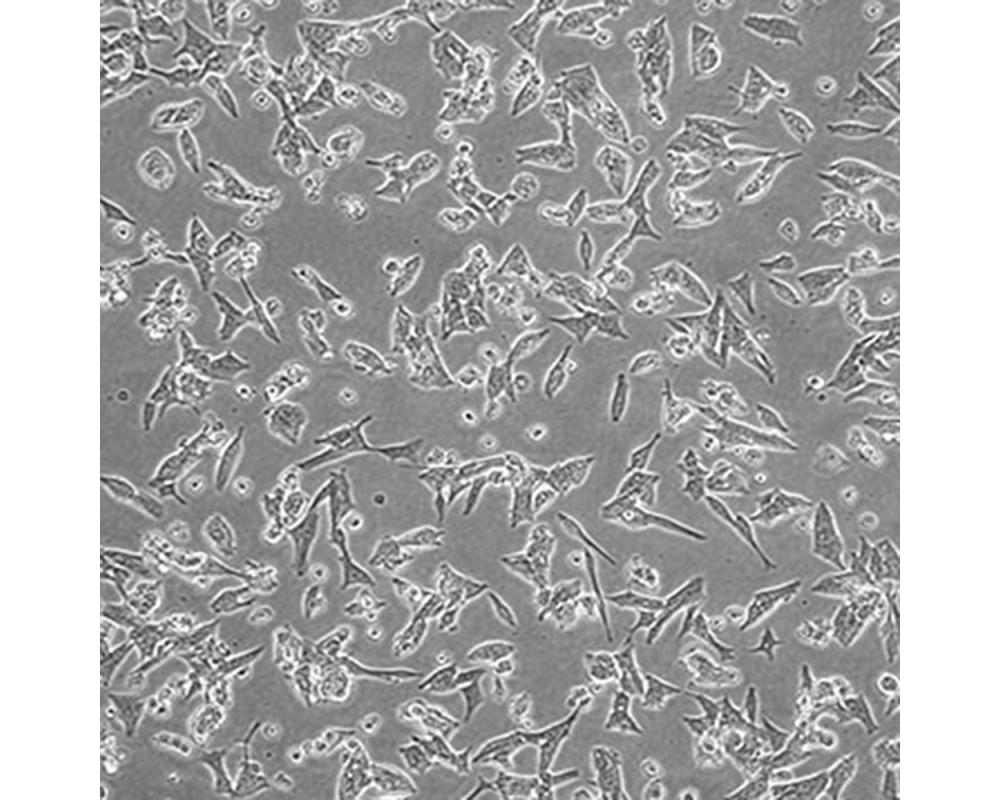

中文名稱 人前列腺癌細(xì)胞

組織來源 前列腺癌;男性

形態(tài)特征 上皮細(xì)胞

生長特性 貼壁生長

特征特性 1997從一位不受激素影響的前列腺癌患者脊椎轉(zhuǎn)移灶中建立了這株細(xì)胞。先在小鼠中進(jìn)行異種移植傳代,隨后進(jìn)行體外培養(yǎng)。體內(nèi)及體外都對(duì)雄性激素敏感。